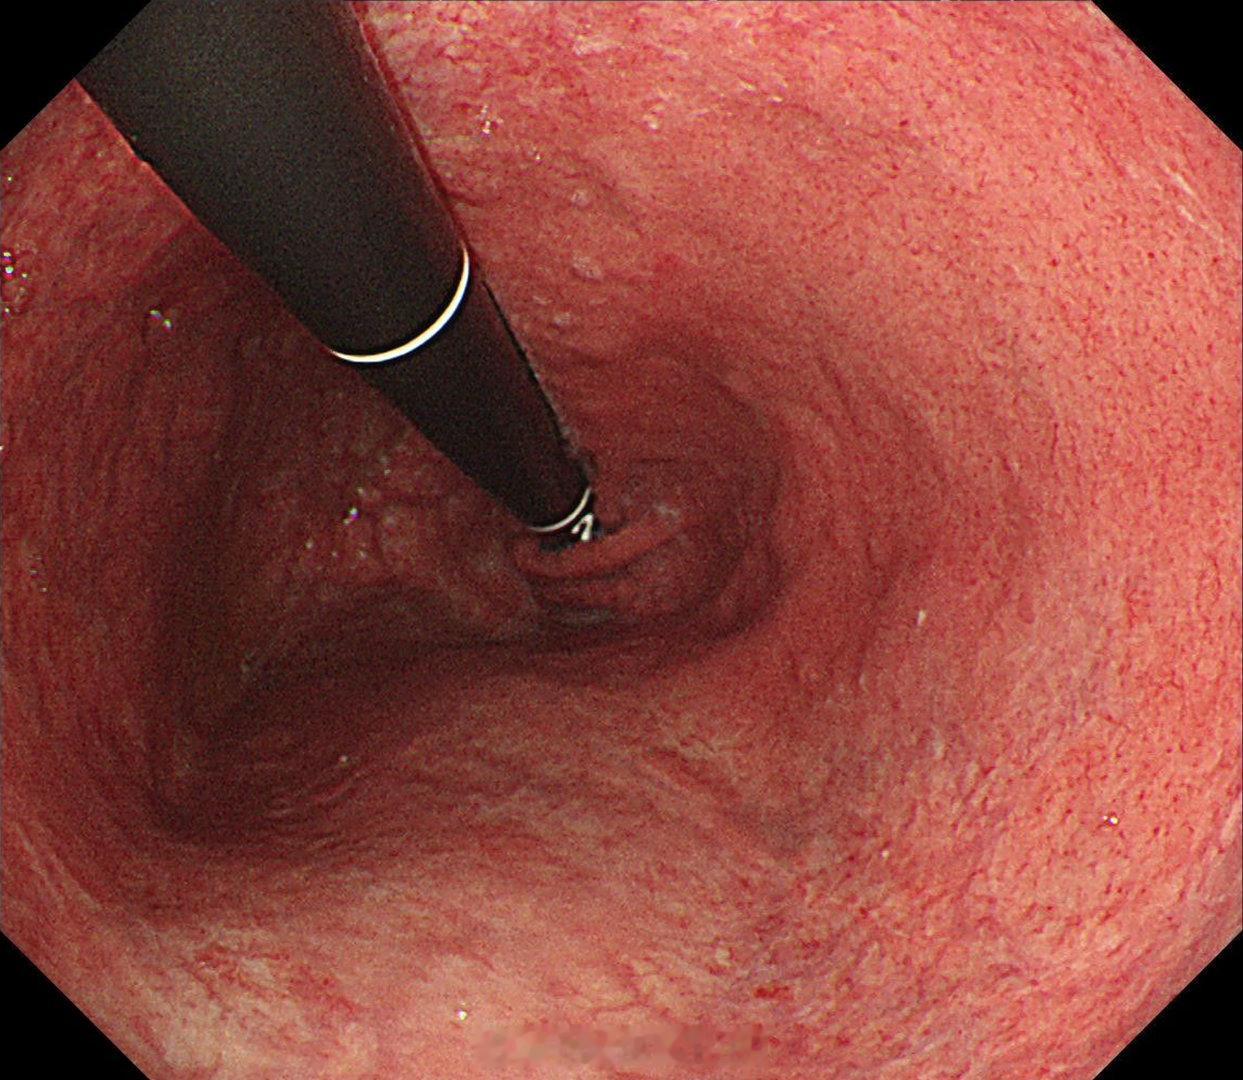

这是个常州来找我会诊的疑难杂症,当地觉得萎缩一塌糊涂,但是活检也没有提示啥病因,一开始我接诊也觉得是自身免疫性胃炎,但是抽血指标都不符合,最后在几块残余正常黏膜表现中看到了点蛛丝马迹,活检加上masson染色确诊是胶原性胃炎,以前不认识的时候这个世界都没这个病,一旦会诊断以后,满眼都是这类病[允悲][允悲][允悲]

这是个常州来找我会诊的疑难杂症,当地觉得萎缩一塌糊涂,但是活检也没有提示啥病因,一开始我接诊也觉得是自身免疫性胃炎,但是抽血指标都不符合,最后在几块残余正常黏膜表现中看到了点蛛丝马迹,活检加上masson染色确诊是胶原性胃炎,以前不认识的时候这个世界都没这个病,一旦会诊断以后,满眼都是这类病[允悲][允悲][允悲]